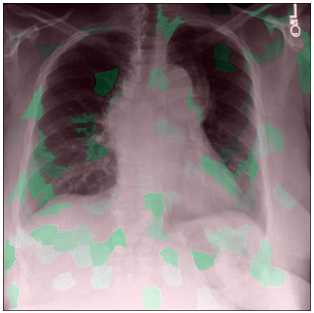

3.3 Interpretability

Post-Hoc Comparisons. We compare our concept-based explanations to post-hoc XAI techniques LIME and SHAP, applied to the baseline InceptionV3 model. The image explanations generated by these techniques disagree with each other and the medical ground truth. We show an example of this observation in Figure 7, where both techniques fail to capture the large mass in the X-ray, and highlight irrelevant regions such as areas outside of the lung as incorrectly important to the classification decision. In contrast, our approach correctly identifies the presence of a mass. More examples are shown in Figure 10.

Refer to caption

(a) Ground Truth

(b) LIME

(c) SHAP

(d) CXR-LLaVA Generated Report

(e) Our Approach

Figure 7: Example of our explanation approach outperforming LIME, SHAP and CXR-LLaVA. Ground truth (a) is a “Large right upper zone mass". LIME (b) and SHAP (c) fail to capture the mass in the X-ray. Most important image regions are bounded by yellow for LIME, and shown in more vibrant green for SHAP. CXR-LLaVA (d) generates a report which wrongly describes the image as non-cancerous. Our approach (e) correctly identifies the presence of a mass.